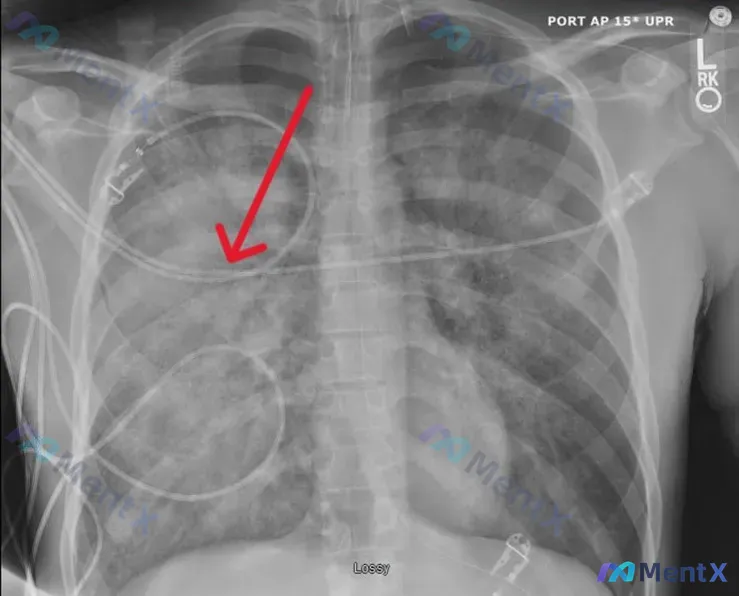

整理了一份术后监护室的床旁胸片资料,术后第1天拍摄,红箭头指的是右肺的局灶实变。 先列目前给出的关键信息: - 时间窗:术后第1天(POD1) - 影像类型:床旁前后位(AP)半卧位胸片,吸气程度略显不足 - 核心影像表现: 1. 双肺野透亮度下降,弥漫性斑片状、云絮状高密度影,肺门区及下肺野明显...